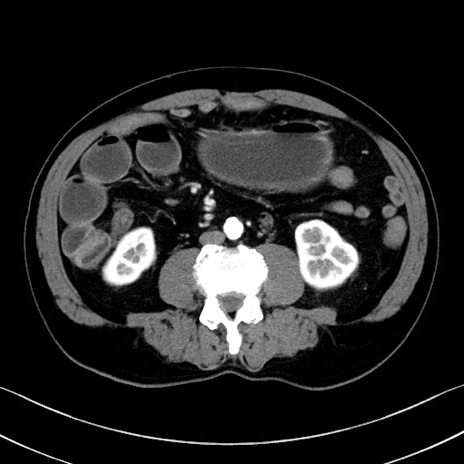

症例35(横断像)

【症例】70歳代 男性

【主訴】腹部膨満、嘔吐

【現病歴】昨日より腹部膨満感出現。本日増悪し、仙痛出現。嘔吐あり、受診。

【既往歴】糖尿病、胆摘後

【身体所見】BP 149/80mmHg、HR 74/min、BT 35.9℃、腹部:膨満、軟、圧痛なし。腸雑音減弱あり。上腹部正中切開瘢痕あり。

【データ】WBC 13500、CRP 1.72